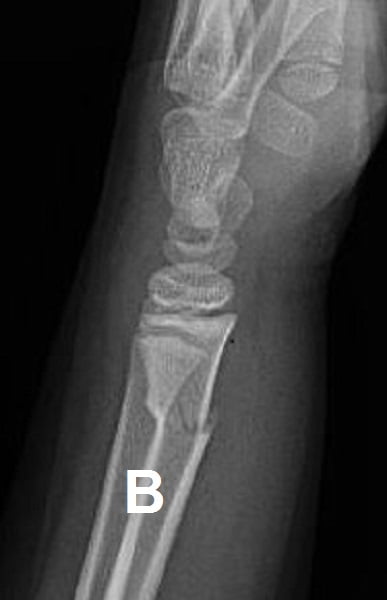

Figure 2: (A) Salter-Harris II distal radius; (B) Greenstick of distal radius

The key caveat is to ensure that the radiological diagnosis of distal radius buckle fracture is correct. Radiographs should be scrutinized for other diagnoses since minimally displaced greenstick and Salter–Harris II fractures of the distal radius may be mistaken for buckle fractures6. These injuries require rigid immobilization and orthopedic consultation.